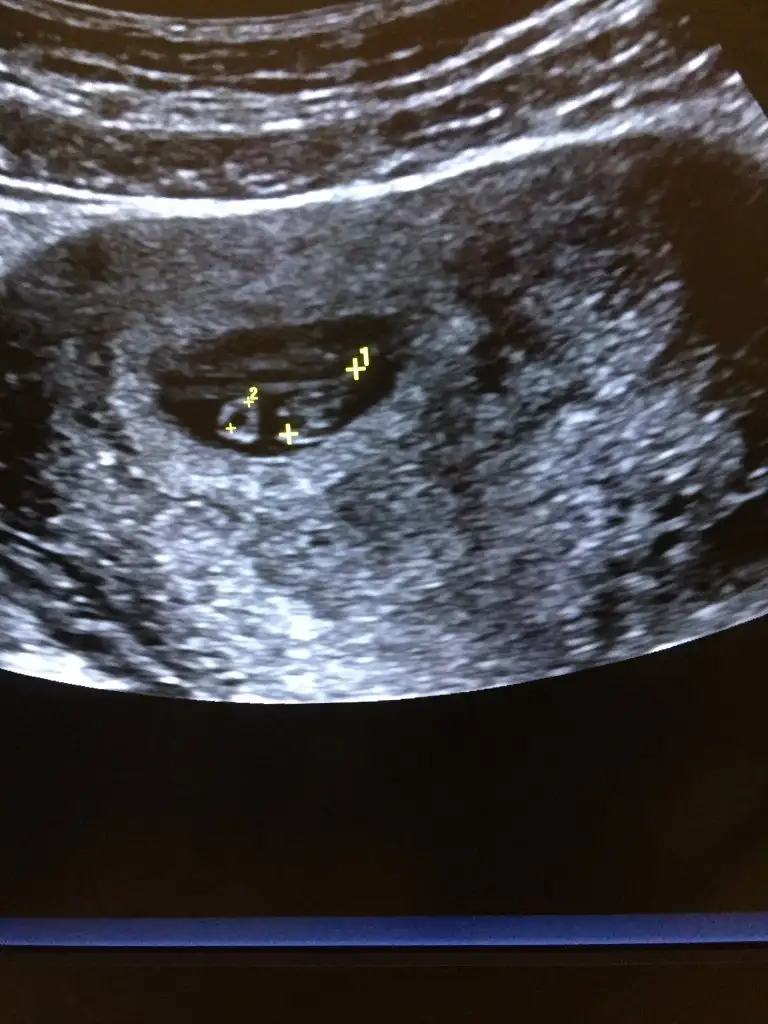

Kızlar 6-7 haftalık olanlarda ultrason görüntüsü varsa rica etsem atabilir mi benim birşey belli olmuyorda merak ettim

7 haftalık ultrason. Sizin belli olmayan nedir? Zaten yolk sac ve beyazlık halinde bir bebek görünüyor sadece bu haftalarda. Çok belirgin olmuyorlar :)

Eklentiler

• 14122805-E1F7-47F8-B554-EBDC4EA5DB25.webp

41,2 KB · Görüntüleme: 52